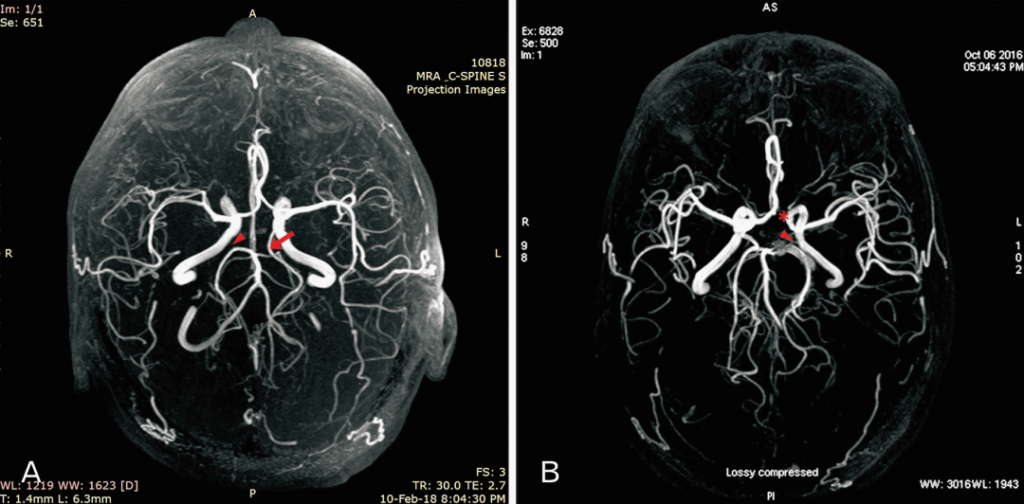

CT scans provide high-resolution images of the brain, making it easier to detect blood vessel narrowing. However, due to the complexity of brain structures, advanced segmentation and annotation techniques are needed for precise diagnosis.

Segmentation divides CT images into regions of interest, isolating blood vessels and detecting narrowed sections caused by plaque buildup.

Annotation involves labeling key features in segmented images, such as the location, size, and severity of stenosis. Accurate annotation benefits both medical professionals and AI systems, aiding in automatic stenosis detection.

Segmentation in medical imaging refers to the process of isolating and highlighting specific areas of a scan, such as blood vessels or abnormal tissues. Annotation involves labeling these segmented areas to help radiologists and AI-powered systems quickly identify problem zones.

Standard CT scans can be difficult to interpret, especially when dealing with intricate brain structures. AI-based segmentation enhances image clarity, allowing doctors to easily distinguish between normal and narrowed blood vessels.